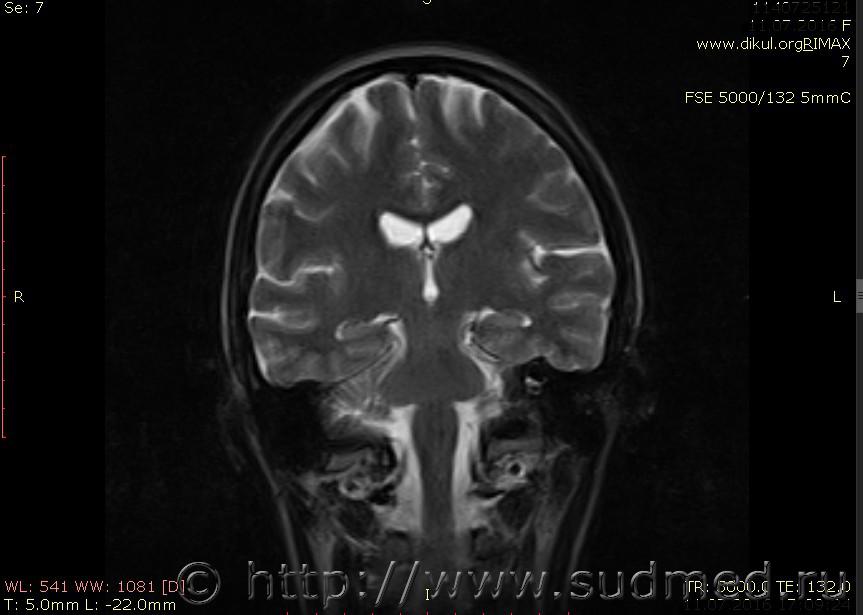

МРТ головного мозга показало: МР-данных за наличие очаговых изменений в веществе головного мозга на момент исследования не выявлено. МР-признаки нарушения соотношения в атланто-осевом суставе. Определяется ассиметрия положения зубовидного отростка С2 относительно боковых масс С1(справа 6,5; слева 4 мм.)

Сама по себе эта информация даёт основания подозревать вывих первого шейного позвонка, но однозначно не свидетельствует о наличии вывиха. Нужно смотреть на снимках наличие реакции со стороны мягких тканей, в т.ч. связочного аппарата, нужно анализировать особенности неврологической патологии, её динамику и проч.

Запрошен электронный вариант снимков из учреждения, где делалось МРТ. Т.к. с самого снимка делать копии не получается,очень мелкие кадры. Завтра попробую вставить в сообщение. (Но СМЭ снимок не смотрел, смотрел только мед.карту, в которой находилось описание МРТ).

Посмотрите пожалуйста снимки, надеюсь на них видны позвонки С1,С2?

Прошу прощения, попробую снова прикрепить файлы. Данные учреждения и пациента убраны.